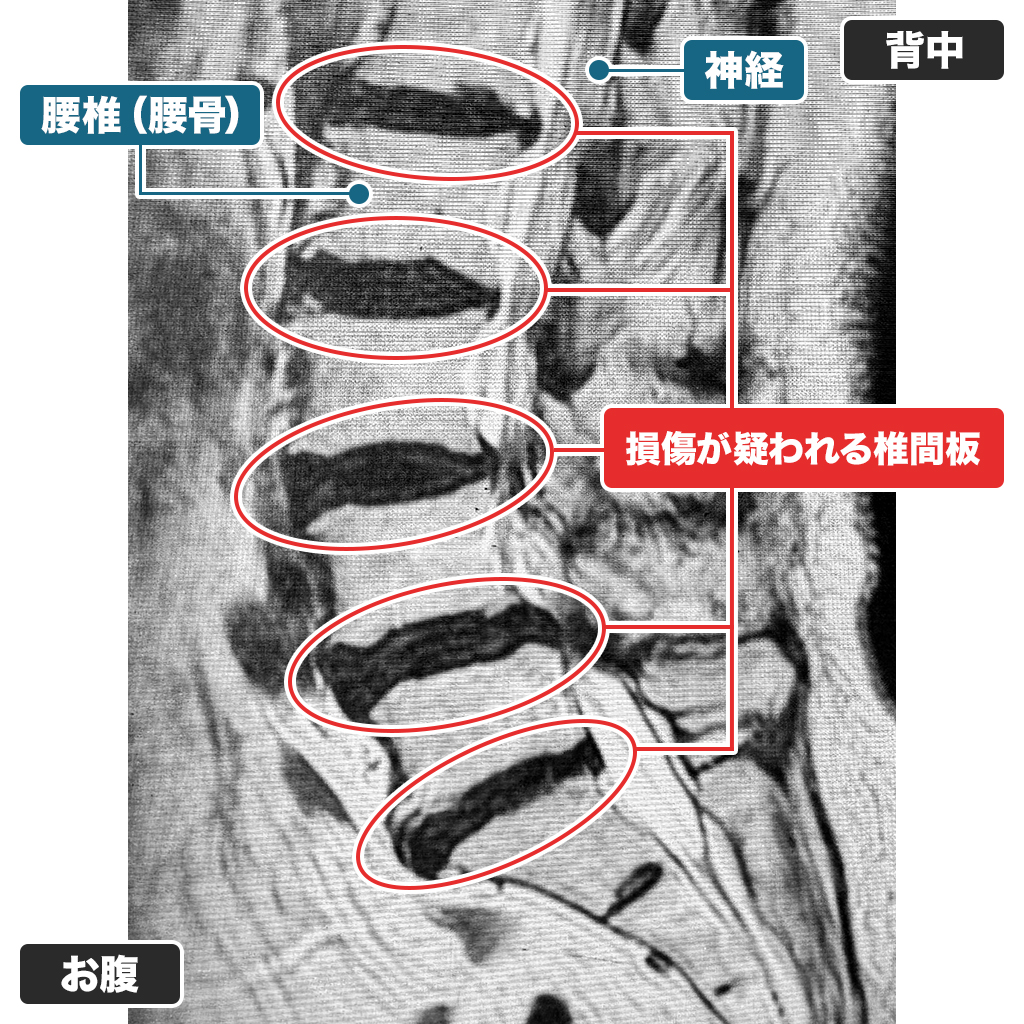

MRI検査

腰のMRI検査です。椎間板はすり減り、神経の通り道である脊柱管も非常に狭くなっています。神経症状と神経学的所見も脊柱管狭窄症に一致します。